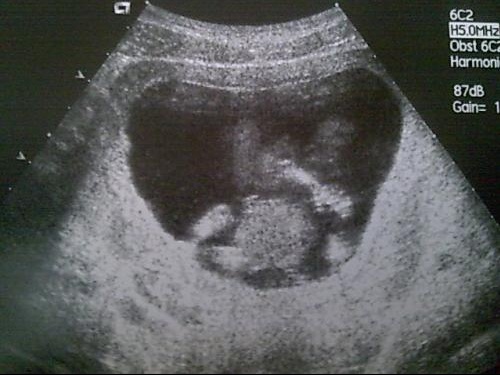

Echographie bébé tete en bas

Echographie bébé tete en bas-Bebe Petite Tete Echographie Forum Une fois, que le bébé se positionne la tête en bas, sa tête reprend une forme un peu plus « normale » et la valeur de son diamètre biparétal se normalise également au passage Je lis par ailleurs que la valeur du diamètre biparétal n'est pas une valeur significative (certainement pour les raisons invoquées cidessus) Coucou, j'ai aussi eu ce C'est le cas, notamment, de ceux qui, à la 3 ème échographie, ne se présentent pas la tête en bas, comme dans la majorité des cas, mais dans l'autre sens Bébé se retourne au 7 ème mois de grossesse normalement !

Il a la tête en bas, et son dos est à gauche et en avant Comment faire pour que bébé ne se retourne pas sur le ventre ?Il a la tête en bas, et son dos est à gauche et en avantTaille du fémur Permet d'estimer la taille du bébé Bébé est placé Tête en bas, Tête en haut ou en siège ( risque de naissance en siège et donc de césarienne) Bébé a commencé sa descente, est placé haut, (risque de naissance tardive) Placenta haut, droite, gauche, bas (risque de césarienne a vérifier à la prochaine échographie) Col ouvert à un doigt